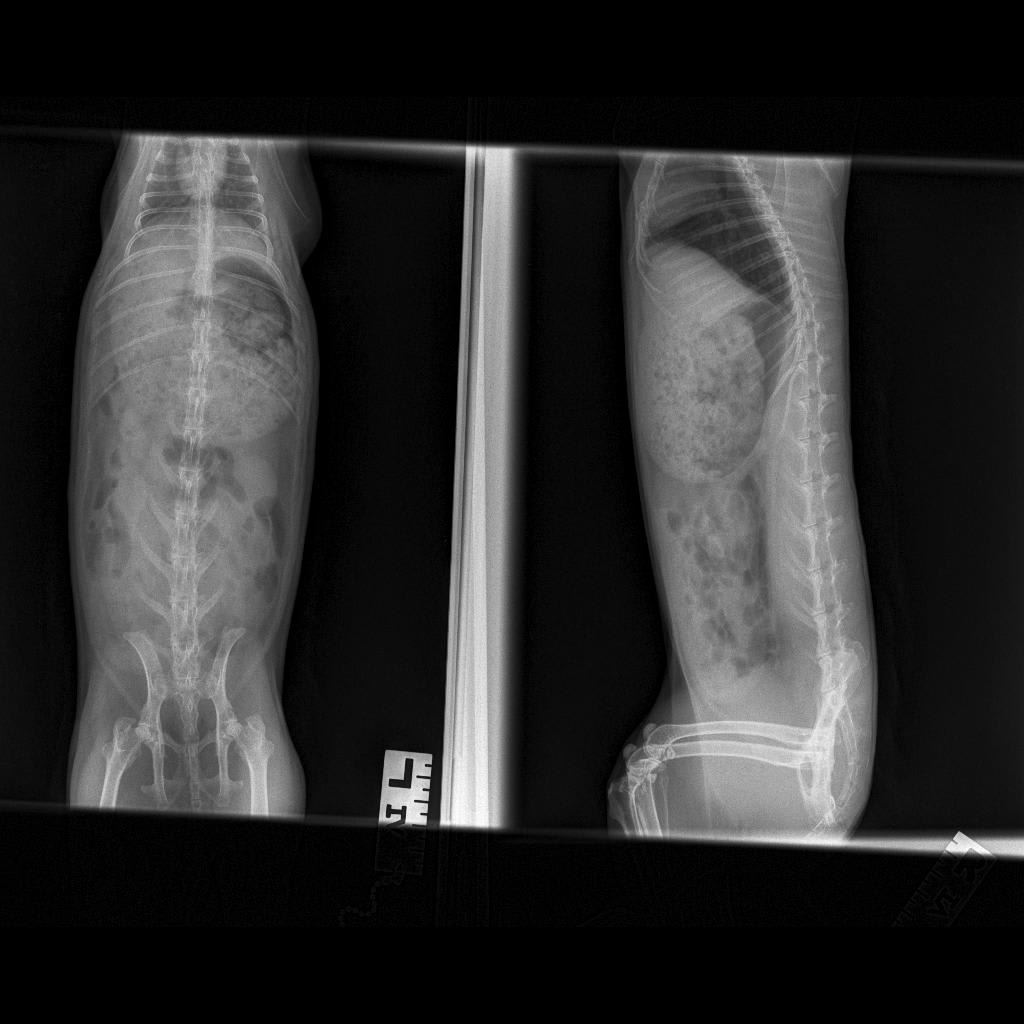

My bunny eats, but he hasn't poop for full 24h. He is lethargic, I saw him eating cecotropes, but they were dry. Yesterday, I gave him 3x simethicone 1.5ml for 3 hours, then continued 1ml for periods 3-6hr. I also gave him probiotic yr and today. Made him drink some water with apple juice and eat wet greens, but he doesn't poop. He also god flax seeds and 0.5ml virgin olive oil. Should we feed him any more, and also is it better to go give him motility drug or give him activated charcoal?

This question includes photos that may contain sensitive content. Click to view.

View more to consider that the photos may include sensitive content.